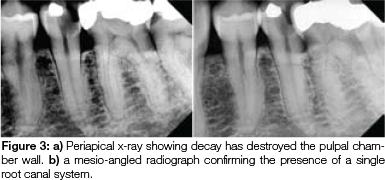

A 66-year old male patient was referred for endodontic treatment and restoration of his lower left second premolar, after he presented with acute irreversible pulpitis and acute apical periodontitis. Radiographic evaluation revealed that the decay had exposed the pulp and that the tooth had a single root canal system (Figure 3a and 3b). An irregular 'keyhole" cross section of the coronal root canal system was observed during access cavity preparation (Figure 4). Working length was determined using the I-pex apex locator (NSK, Nakanishi, Japan) and confirmed with a periapical radiograph (Figure 5). The canal was prepared with the Reciproc R25 (VDW) and, following apical gauging, the canal was enlarged to a 35, 4% taper using the BT3 Race file (FKG Dentaire, Switzerland). During instrumentation, the canal was irrigated with 3.5% sodium hypochlorite (Jik, Reckert-Benkieser, South Africa). The Endovac (Axis/Sybron, Coppel, Texas) apical negative pressure irrigation system was used to optimise the volume of irrigant delivered through the root canal system. Ultracal (Ultradent, Utah, USA), a non-setting calcium hydroxide was used as an inter-appointment medicament in the root canal.